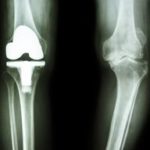

膝の人工関節には部分的に人工物に置き換える方法である単顆人工膝関節置換術(U K A:Unicompartmental Knee Arthroplasty)と、関節を全体的に人工関節に置き換える方法である全人工膝関節置換術(T K A:Total Knee Arthroplasty)があります。一般的に部分的に人工関節を置き換える手術は、変形の程度が内側か外側に限定されている場合に行われます。しかし症状が末期まで進行すると、関節の変形は全体まで広がり、全体的に人工関節を置き換える方法が選択されます。